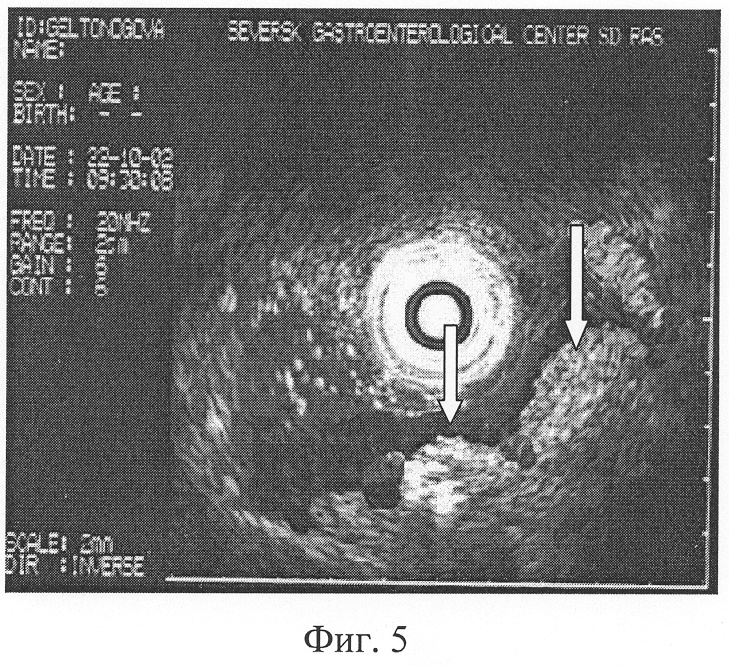

При наличии грубых извитых складок слизистой, их атипической перестройки, ширина которых в теле и антральном отделе желудка более 6 мм, по большой кривизне, в своде и синусе более 10 мм (Фиг.4), соотношении минимальной к максимальной высот желудочной складки от подслизистого слоя, приближающемся 1:1,5, наличии желудочных полей правильной округлой формы, диаметром 3-5 мм (Фиг.5) диагностируют поверхностный гастрит.

В результате проведенного исследования установлено, что слизистая пищевода обычной окраски. Кардия полностью смыкается. В желудке слизи нет. Слизистая желудка в антральном отделе умеренно гиперемирована, блестящая, дефектов слизистой нет, в антральном отделе желудка складки имеют грубый, извитый характер, ширина складок в антральном отделе желудка от 6 до 8 мм, по большой кривизне складки расположены типично, ширина их не превышает 10 мм (Фиг.4). Соотношение минимальной к максимальной высоте желудочной складки от подслизистого слоя приближается 1:1,5. Желудочные поля имеют неправильную округлую форму диаметром 4 мм (Фиг.5). Привратник сомкнут, проходим. Луковица двенадцатиперстной кишки не деформирована, патологии со стороны двенадцатиперстной кишки нет. Заключение: Хронический поверхностный гастрит, обострение.

Фиг.5. Б-ной А. 36 л. Эндоскопическая гастросонография. Желудочные поля неправильной округлой формы, диаметром на различных участках до 4 мм (обозначены стрелками).